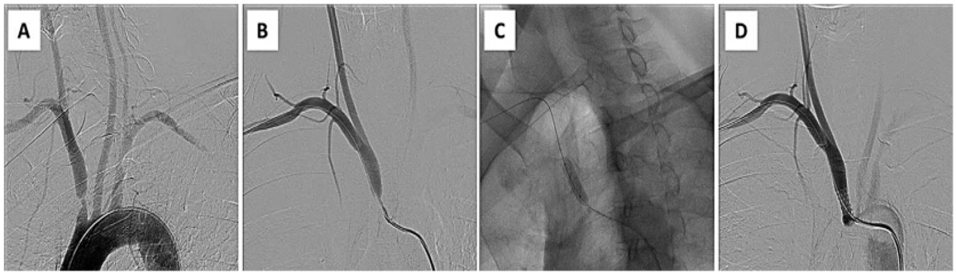

② 无保护逆行介入

操作流程:0.014in导丝进入颈内动脉 → 跟进保护装置 → 球囊扩张/支架植入 → 回撤前导引导管跨越病变。